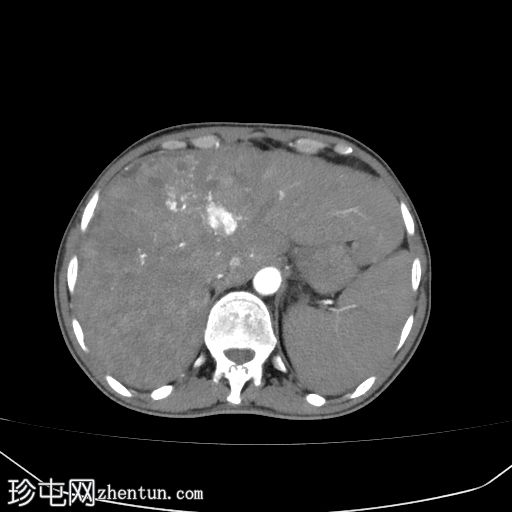

2.jpg

轴位增强扫描

动脉期

肝硬化征象包括表面和实质结节、实质异质性、右后肝切迹征和容积重分布。

门静脉可见肿瘤血栓,表现为血栓强化。

肝脏可见无数细小病灶,动脉期呈非环状强化,门静脉期呈消退,提示弥漫性肝细胞癌。

其他发现包括腹水和左侧肾上腺可疑增厚。